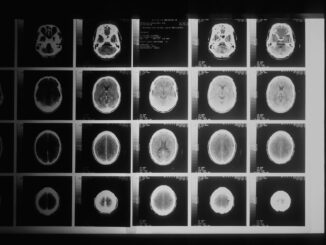

Abstract Artificial Intelligence (AI) is fundamentally reshaping the landscape of medical diagnostics, offering unparalleled advancements in the precision, efficiency, and accessibility of disease detection, characterization, and management. This comprehensive report meticulously explores the transformative potential […]